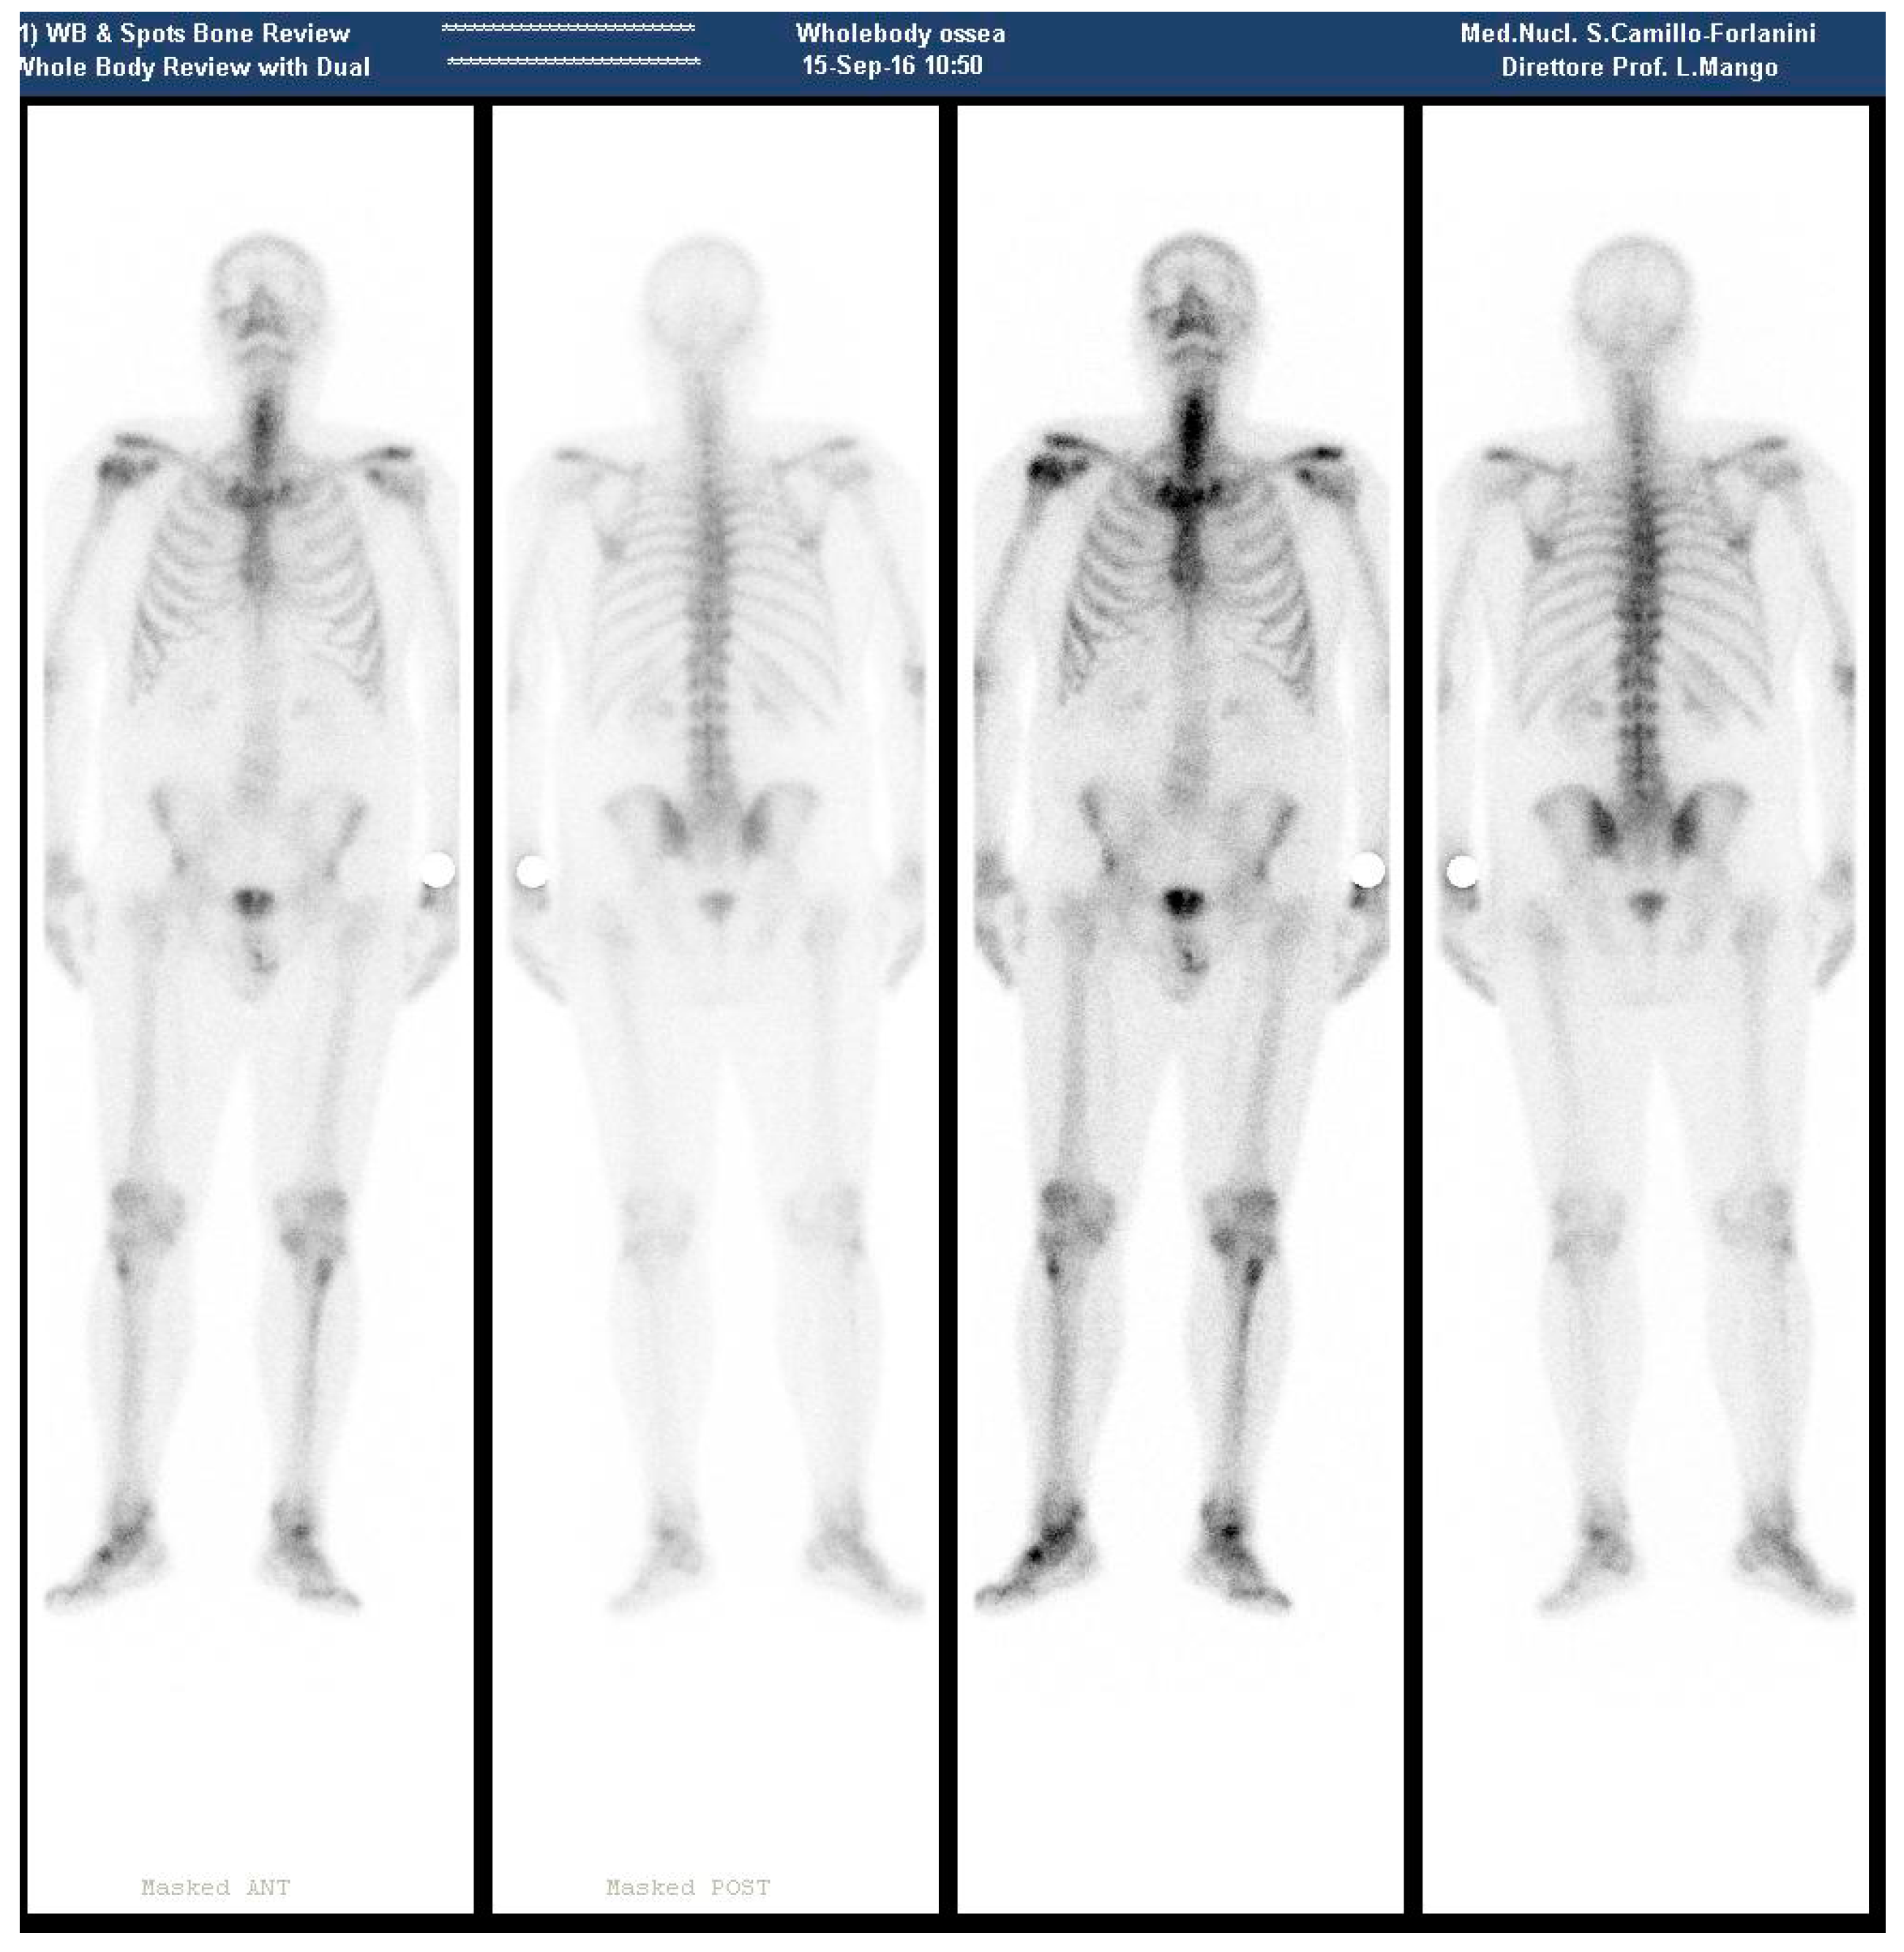

During September 2016, a negative bone scan was obtained, except for a mild tracer accumulation on the surgical neck of the right humerus (Figure 2).

Figure 2.

(September 2016—Bone scan 4 months after 223RaCl2 last cycle, with no metastatic site, except for the surgical neck of the right humerus).